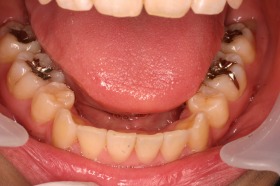

歯の矯正治療 症例ビフォー&アフター

ご覧の症例は出っ歯を矯正治療でキレイにしたケースです。

ご覧の矯正歯科治療の場合は、抜いて矯正歯科

治療していますが東京世田谷矯正歯科センターでは

非抜歯矯正歯科治療をベースにしています。

どうしても抜かないとキレイにならない場合のみ

抜歯して矯正歯科治療しています。